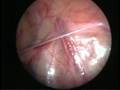

The commonly misleading history given by the parents is that the child may have had a trivial trauma or an insect bite. However, for the clinician the golden rule should be ‘Any acute scrotum is testicular torsion unless proved otherwise’. Investigations like ultrasound and color doppler may be done to help in the diagnosis. However, in the event of any doubt, it is safest to do a surgical exploration of the scrotum. The other uncommon causes of acute scrotum are acute epidydymo orchitis, scrotal abscess, idiopathic scrotal oedema and torsion of appendix of the testis. ●

Torsion of Left Undescended Testis (Pre operative and Operative Photo)

Torsion Testis (Pre and Per operative photo)